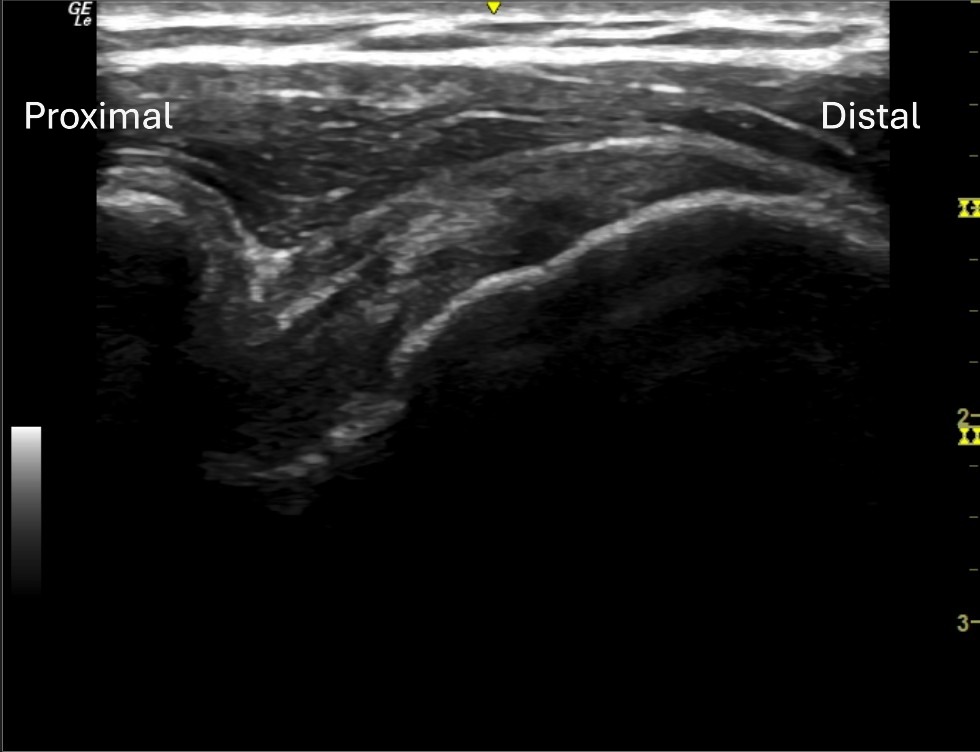

Unlabeled long axis view of the anterior supraspinatus tendon at the articular surface.